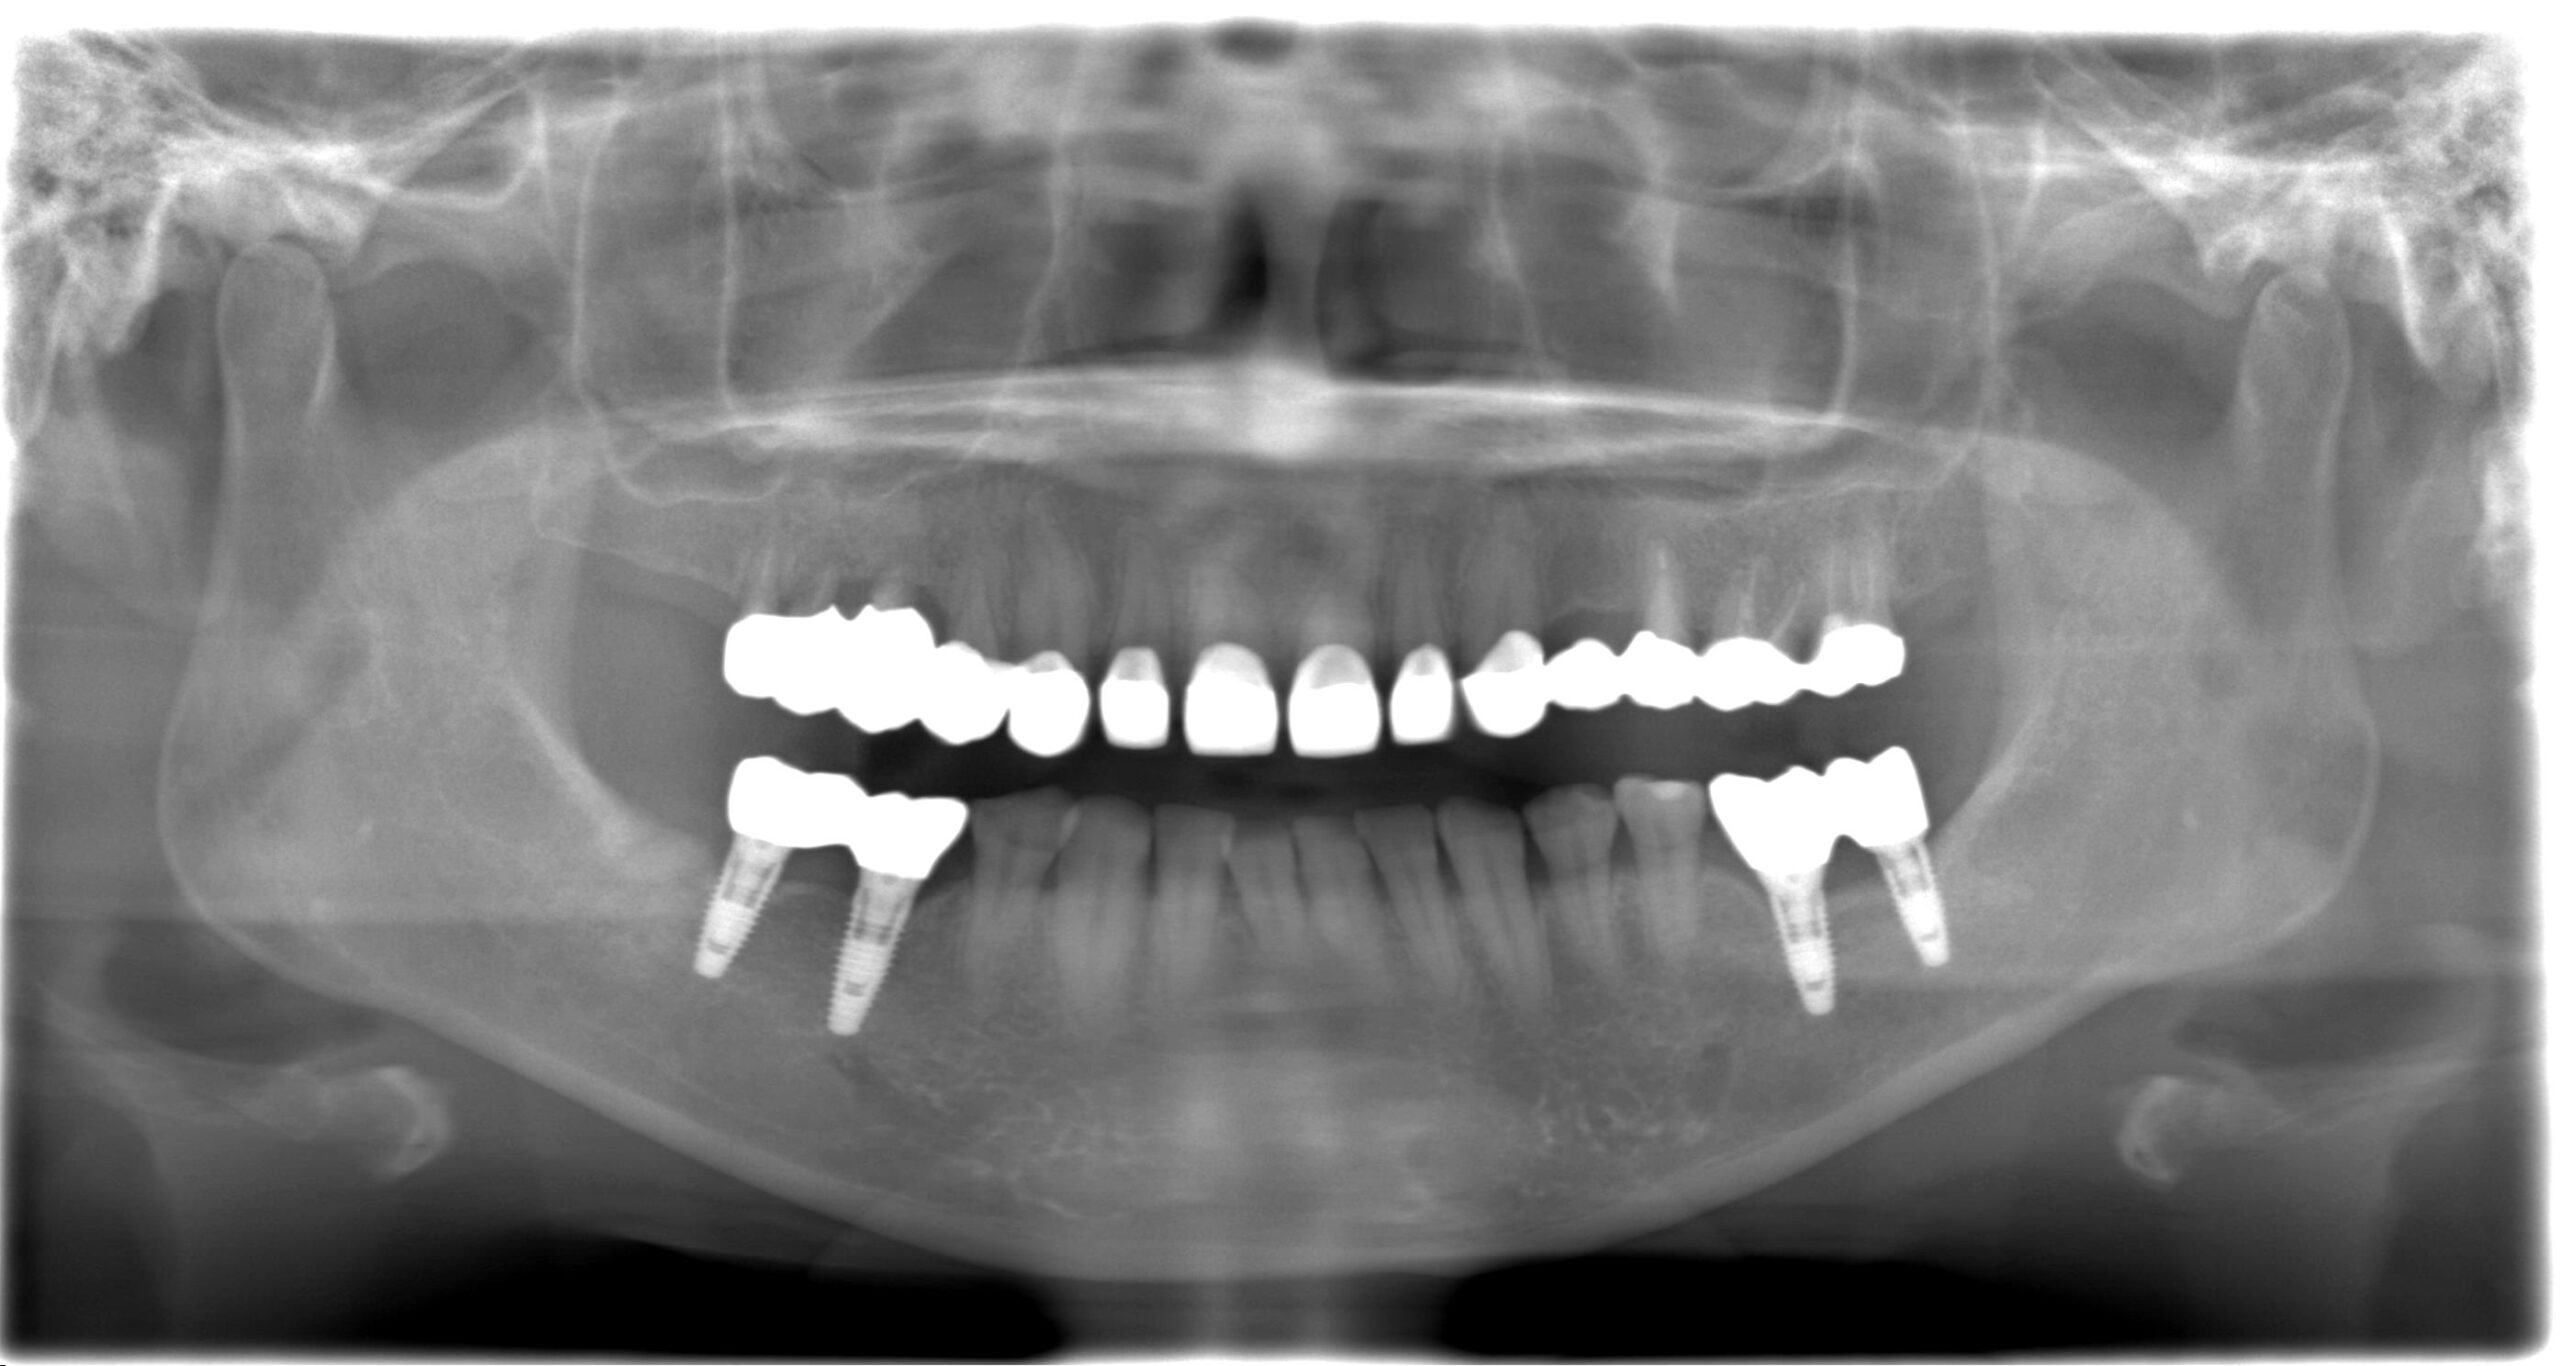

症例02

70代 男性 咬み合わせが強く多くの歯がすぐに壊れる

| 主訴 | 咬み合わせが強く、治療をしてもつくった歯がすぐに壊れる。 他院ではインプラントをいれることも難しいため、断られた。 |

| 年代・性別 | 70代 男性 |

| 治療部位 | 下顎両側 5,6 上顎右側 4 6のインプラントブリッジ ※全顎的に、臨床的歯冠長延長術(クラウンレングスニング)を行い、セラミッククラウンの強度を増しています。 |

| 治療費用 |

インプラント 440,000円×6本 |

| 手術回数 | 下顎1回 上顎1回 |

| 治療期間 | 下顎6ヶ月 上顎6ヶ月 |

| 手術時間 | 下顎90分 上顎60分 |

| 治療回数 | 下顎1回 上顎1回 |